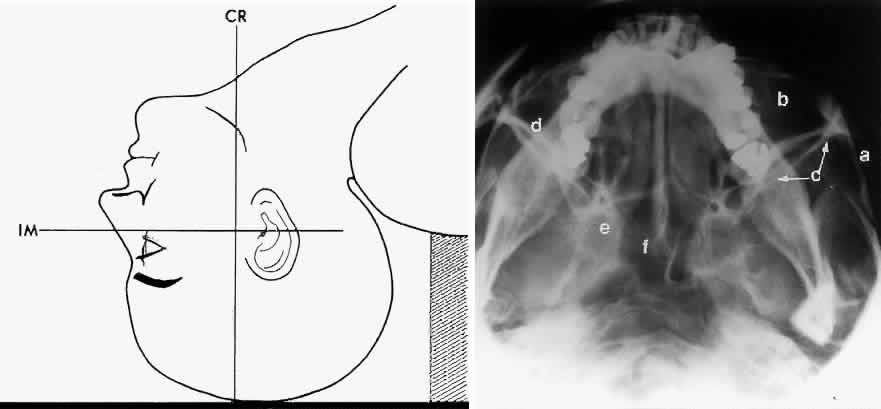

The basal projection (Fig. 5) for the evaluation of the sphenoid sinus and skull base was described initially by Arthur Schuller12 in 1905 and later popularized in this country by Bowen.13 This projection is obtained with the patient's neck extended either in the supine or upright position. The top of the head is placed so that the infraorbitomeatal line is parallel with the x-ray cassette. The x-ray beam is directed at right angles to the infraorbitomeatal line.5,6 This view shows the lateral walls of the orbit and maxillary sinuses well. The nasopharynx, pterygoid plates, pterygopalatine fossa, and the sphenoid and ethmoid sinuses may also be inspected. Because of the extreme head position, any history of a neck injury is a contraindication to this radiologic study.

Fig. 5. A. Schematic showing positioning for a basal projection. (CR, central ray; IM, infraorbitomeatal line) B. Radiograph of a basal projection. (a, zygomatic arch; b, orbit; c, lateral orbital wall; d, posterior wall of maxillary sinus; e, pterygoid plate; f, sphenoid sinus) (A; Rao VM, Gonzalez CF: Plain film radiography and polytomography of the orbit. In Gonzalez CF, Becker MH, Flanagan JC [eds]: Diagnostic Imaging in Ophthalmology, pp 1–7. New York, Springer Verlag, 1986)